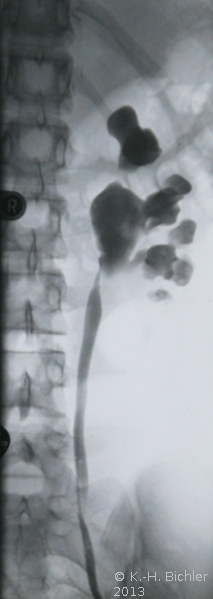

Sonographiebeispiele: Harnstau infolge Ureterabgangsstenosen (Abbildung 6a,b).

Bei Harnstaus ist eventuell eine retrograde Sondierung mit Sicherung einer Ureterabgangsstenose angezeigt (Abbildung 8) (

s. Bildgebende Verfahren/Retrogrades Pyeologramm).